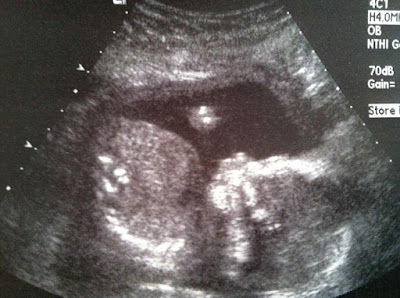

Here are some ultrasound pictures taken of Baby Girl at the anatomy scan today.

![]() |

| Profile shot |